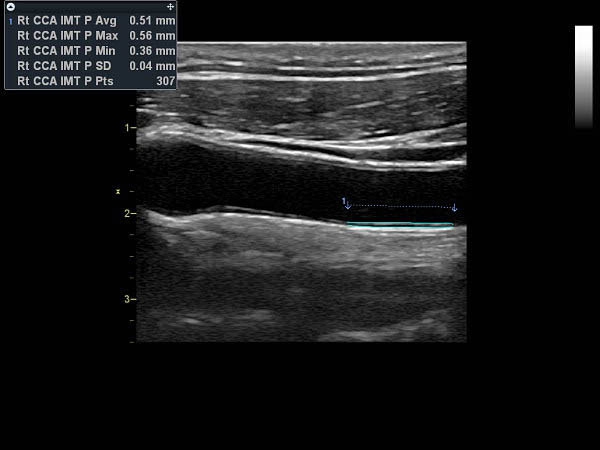

• AutoEF (Auto Ejection Fraction) — функция автоматической недоплеровской количественной оценки глобальной сократительной функции левого желудочка с выделением зоны интереса по технологии спекл-трекинга.

IMT (Intima Media thickness):

Да